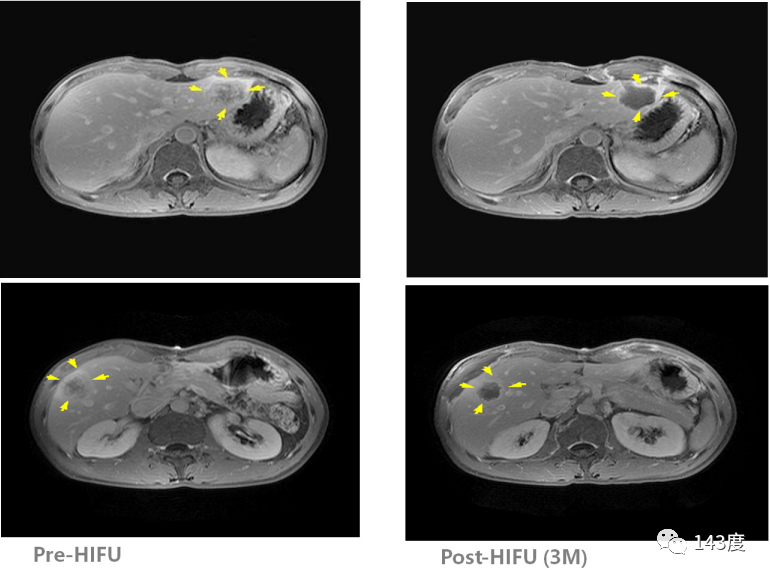

Liver Cancer Treatment Case 4:

Patient: Male, 33 years old, metastatic liver cancer

One lesion found in each lobe of the liver. HIFU treatment performed simultaneously, resulting in tumor necrosis and absorption three months post-surgery.